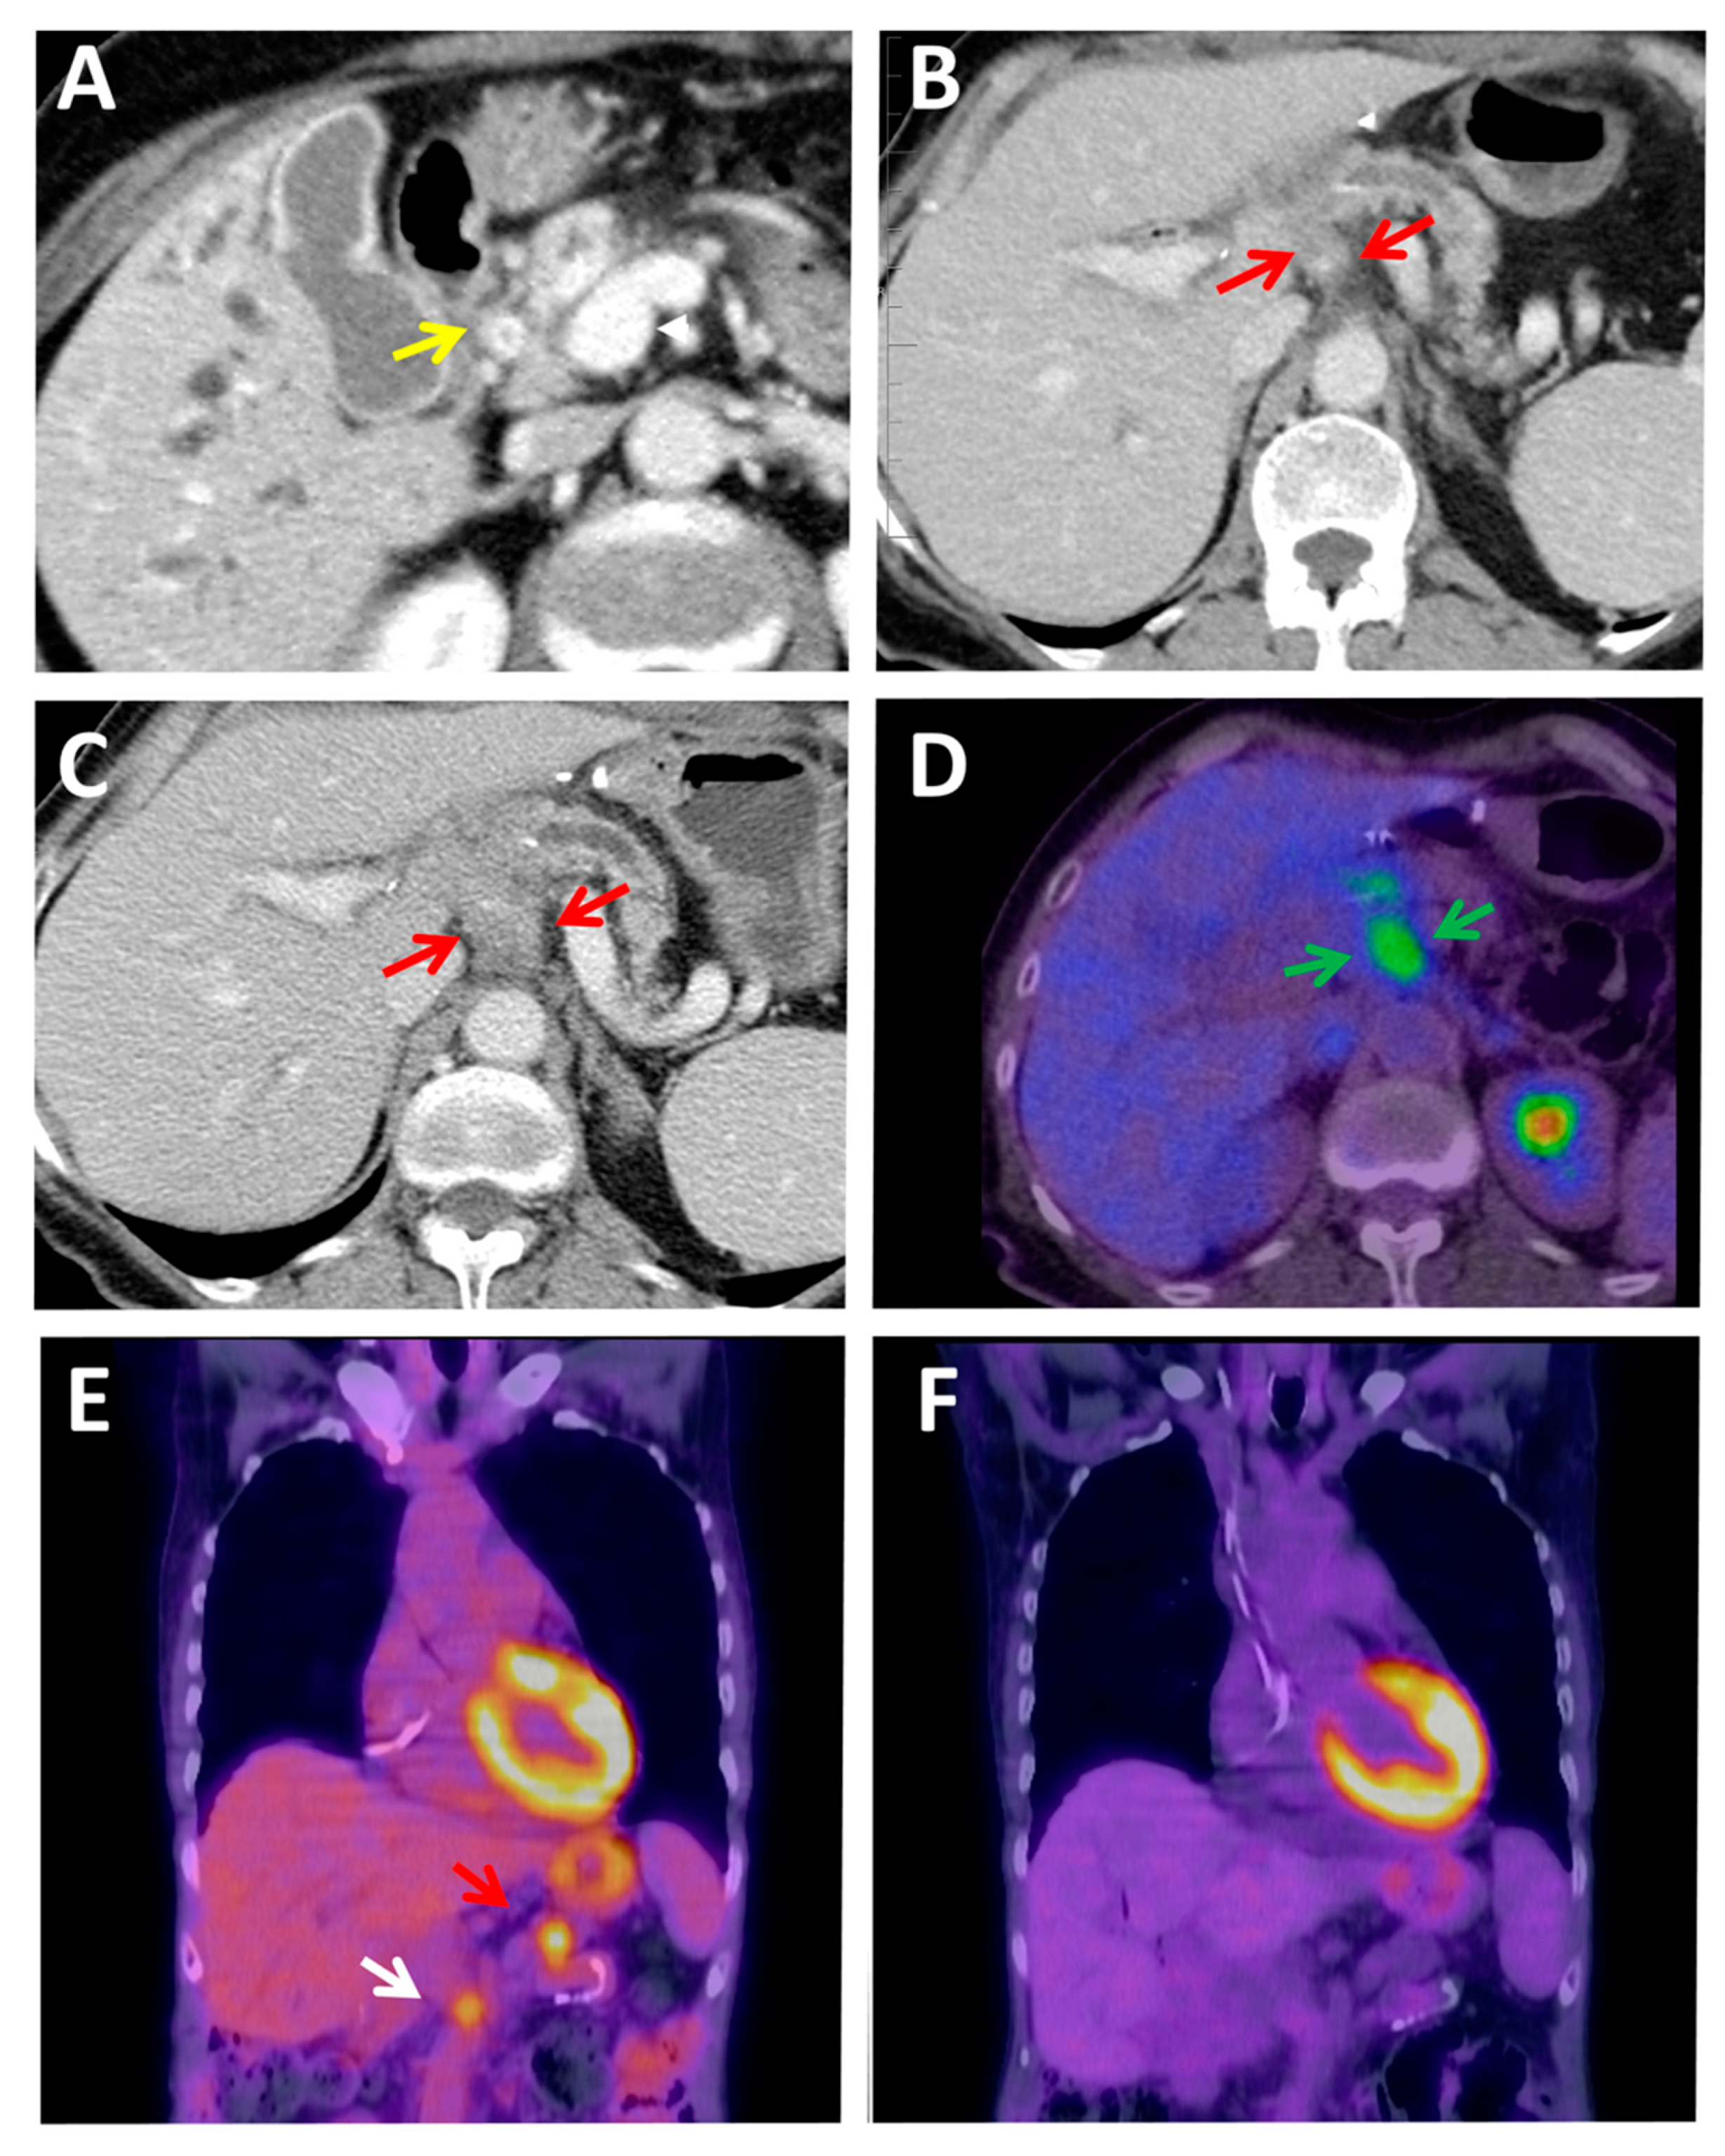

2.4. PET Hybrid Imaging